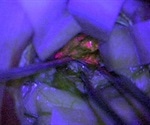

Special chemical that makes brain tumours glow pink to help neurosurgeons operate